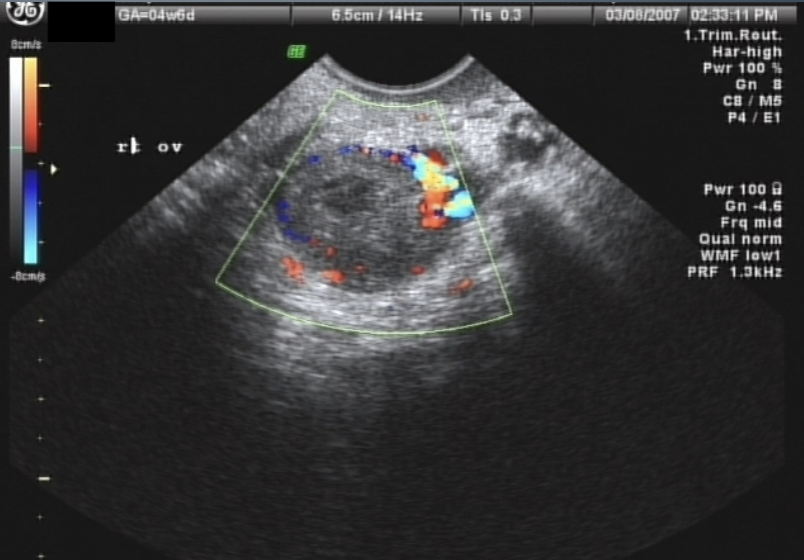

Corpus Luteum “Cyst”

as dominant follicle ruptures, corpus luteum develops (1.5-2.5 cm)

not considered a true cyst until >3cm, may measure up to 6-8 cm in diameter

Unilateral and unilocular

Corpus Luteum “Cyst” U/S appearance:

hypoechoic w/ irregular or thick borders around a central anechoic area

may contain hemorrhage

demonstrates peripheral blood flow → “Ring of Fire” sign

Corpus Luteum “Cyst” signs / symptoms:

pain

nausea

vomiting

enlarged, tender ovary